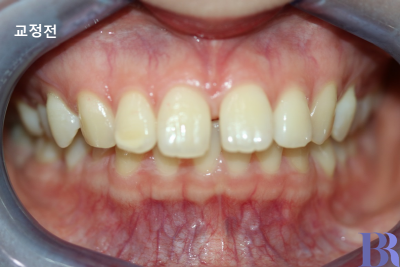

과개교합 양상으로 인해

윗니가 아랫니를 깊게 덮고 있으며

그로 인해 위에 앞니

사이에 공간이 발생했네요.

발치교정 : 하악 교정전 모습